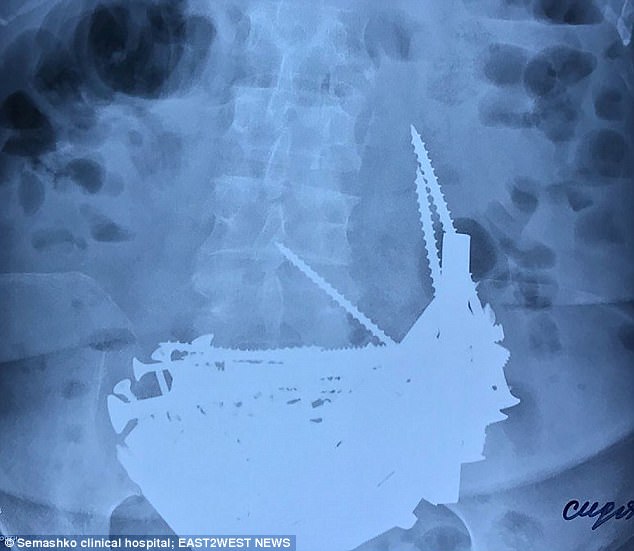

Μία μέρα όμως εισήχθη στο νοσοκομείο με πολύ υψηλό πυρετό. Όταν οι γιατροί έκαναν ακτινογραφίες έπαθαν «σοκ» και την οδήγησαν αμέσως στην πόρτα του χειρουργείου.

Βλέπετε, είχε καταπιεί 152 μεταλλικά αντικείμενα όπως βίδες, καρφιά και κολιέ!